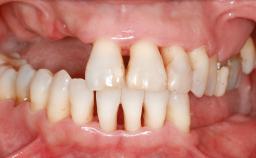

Guided Bone Regeneration (GBR) with a Particulated Autologous Graft and a ePTFE-Reinforced Membrane for Vertical Augmentation of a Single-Tooth Edentulous Space in the Esthetic Zone

A 47-year-old Caucasian woman with a single-tooth edentulous space at the site of the left maxillary canine was referred for treatment. She had undergone traumatic extraction of this impacted canine several months before referral. Her chief complaint was the dissatisfying appearance of her smile. The patient desired a stable and esthetic rehabilitation of the site. Her dental history showed no evidence of periodontal disease or bruxism. She had no systemic diseases, was not taking any medications, and did not smoke. The extraoral examination revealed a high lip line and an inadequate soft-tissue volume at the defective canine site. Large black triangles were visible between the canine and its adjacent teeth.

| Soft Tissue Anatomy | Intact | Defective | |

| Bone Volume | Horizontally and vertically sufficient | Horizontally deficient | Deficient vertically or deficient vertically AND horizontally |

| Soft Tissue Contour and Volume | Significantly deficient |